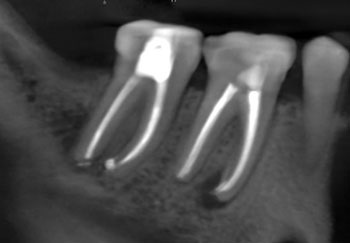

Case 1:A J-shaped lesion

Tooth #30 had a diagnosis of previous root canal treatment with symptomatic apical periodontitis. The mesial root had a classic J-shaped radiographic lesion and a narrow probing defect from the buccal furcation to the root apex. No crack could be seen on what little root surface was visible. The likelihood of VRF, or the possibility of a failing root canal with a chronic apical abscess, were discussed. The latter could be treatable. The plan was to attempt re-treatment after internal inspection for a possible VRF.

Fig. 1: Preoperative PA.

Fig. 2: Postoperative PA.

Fig. 3: Recall PA.

Fig. 4: Recall CBCT.